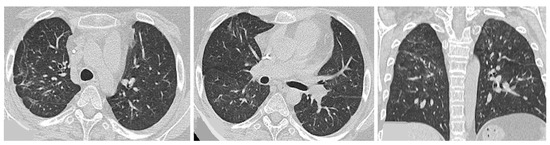

- Chronic progressive fibrosing ILD (reticulation and honeycombing with minimal GGOs on HRCT scans, related to fibrotic NSIP or UIP) [43];

| Lesions | GGO, reticulations, consolidations | consolidations, GGOs | |

| Distribution | Homogeneous; lower lung lobes, along bronchovascular bundles and lung periphery; loss of volume of lower lobes | Patchy; peripheral lower lobes or along the bronchovascular bundles | |

| CT pattern | NSIP OP NSIP-OP UIP DAD-unclassifiable | 50% 20% 25% 10% +/− | 20% 50% 25% <5% ++ |